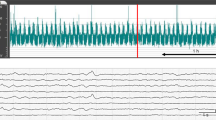

Amplitude-integrated electroencephalography

Neural activity was measured by aEEG (Nicolet One; Cardinal Health, Inc., Dublin, OH). All electrical devices and the copper mesh shield were grounded. The signal was displayed on a semi-logarithmic scale at a low speed (6 cm/h). Measurements were conducted every second. Gold-plated electrode needles were placed at the P3 and P4 positions, which corresponded to the left and right parietal regions of the head. A maximum amplitude <5 µV was defined as low-amplitude EEG (LAEEG) (Fig. 1a). As shown in Fig. 1b, a minimum amplitude >5 µV and a maximum amplitude >10 µV were defined as continuous normal voltage, whereas a minimum amplitude of 3–5 µV and a maximum amplitude >10 µV were defined as discontinuous normal voltage. Traces with continuous normal voltage or discontinuous normal voltage backgrounds were classified as normal aEEG background (aEEG-BG). A maximum amplitude of 5–10 µV was defined as continuous low voltage. A minimum amplitude <5 µV and a maximum amplitude >25 µV were defined as burst suppression. Recurrent seizures lasting more than 5 min were defined as SE, in the same way as in humans.15 Traces with LAEEG, continuous low voltage, burst suppression, and SE backgrounds were classified as abnormal aEEG-BG. We defined “Sz” as any seizure that occurred at least once but did not fit the definition of SE from the previous evaluation period to the current evaluation period (e.g., if single seizure(s) occurred from 3 to 6 h after HI insult, the evaluation at 6 h was considered to be Sz). Using the above evaluation method, the percentage of piglets with an abnormal aEEG-BG, aEEG-BG+Sz, and SE at 24 h after HI insult and the duration of SE (Fig. 1c) were examined in each group. All EEG findings were assessed after the experiment by a single rater (Y.S.) who did not have information about the intervention. In addition, all seizures were confirmed by raw EEG.

Representative example of aEEG at the initial phase of HI insult and LAEEG (a), aEEG background patterns of piglets (b), and representative example of aEEG with SE within 24 h after HI insult (c). a A maximum amplitude <5 µV was defined as LAEEG. The green zone indicates the HI insult, the red line indicates the start of resuscitation (Res), and the blue zone indicates LAEEG. b Normal aEEG background (aEEG-BG): continuous normal voltage and discontinuous normal voltage. Abnormal aEEG-BG: continuous low voltage, burst suppression, and status epilepticus (SE). c Convulsions lasting more than 5 min were defined as SE (orange zone).